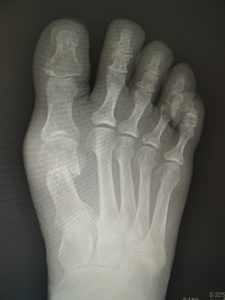

真田理事長による手術の様子。外反母趾|症例 (左から 手術前、手術後、ワイヤ抜去後)

33歳 男性